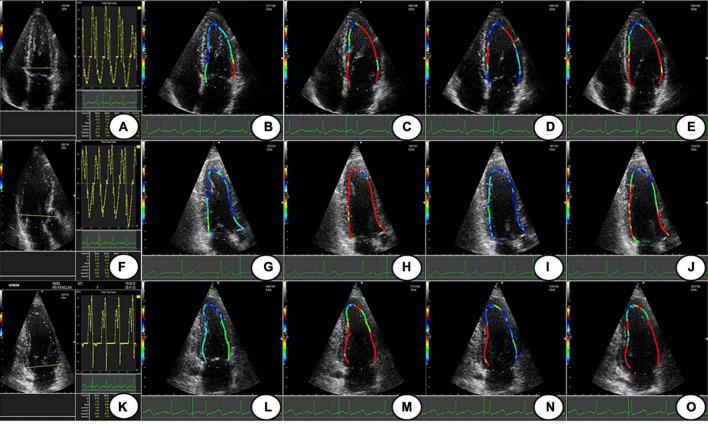

Diastolic wall shear stress (WSS), assessed by using vector flow mapping (VFM), is the result of the interaction between the blood flow and the ventricular wall. This study aimed to evaluate the trend of left ventricular (LV) WSS in normal subjects.

A total of 371 healthy volunteers were recruited and divided into four age groups (group I: 18-30 years; group II: 31-43 years; group III: 44-56 years; group IV: 57-70 years). LV WSS of different age groups was measured at each diastolic phase (P1: isovolumic diastolic period, P2: rapid filling period, P3: slow filling period, and P4:atrial contraction period) to evaluate the change trend of LV WSS. In each age group, LV WSS coincided with a trend of increasing-decreasing-increasing during P1-P4 ( < 0.05). Besides, among groups I, II, III, and IV, WSS of anterolateral, inferoseptal, and anteroseptal in P1 and WSS of inferolateral, inferoseptal, and anteroseptal in P4 all showed an increasing trend with age ( < 0.05). Regarding sex differences, women had greater diastolic WSS compared to men ( < 0.05).

LV WSS showed a regular variation and had specific age- and sex-related patterns in different diastolic phases.